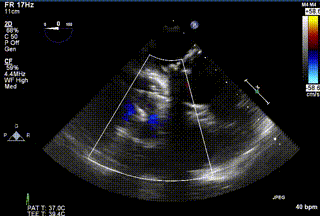

2021年12月24日,復(fù)旦大學(xué)附屬中山醫(yī)院葛均波院士團隊成功應(yīng)用LuX-Valve Plus為一例極重度三尖瓣反流(TR)合并房顫、房缺的患者完成了經(jīng)血管三尖瓣置換術(shù),這是在前基礎(chǔ)上,本周完成的第三例經(jīng)血管三尖瓣置換手術(shù),葛均波院士、周達(dá)新教授等與心外科魏來教授、賴顥教授,心超室的潘翠珍教授、李偉教授及麻醉科的郭克芳教授共同完成了本周手術(shù),均獲得圓滿成功!患者術(shù)后超聲顯示無TR,臨床癥狀明顯改善。本周手術(shù)的成功也為LuX-Valve Plus救治性臨床研究添上了濃墨重彩的一筆。

三例患者入院后,葛均波院士團隊周達(dá)新教授、潘文志教授、張源博士、陳莎莎博士及心超室的潘翠珍教授、李偉教授對患者的情況進行詳細(xì)評估和討論,最終決定為三例患者選擇LuX-Valve Plus40mm、50mm和50mm型號的瓣膜進行手術(shù)治療。手術(shù)后即刻拔除氣管插管,術(shù)后患者三尖瓣反流癥狀得到顯著改善,復(fù)查心超結(jié)果顯示人工三尖瓣瓣膜支架固定穩(wěn)定,瓣葉關(guān)閉形態(tài)未見異常,未見明顯反流。